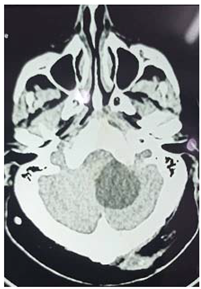

#Case 3:

This is 50 years male, empolayer, heavy smoker, presented to neurosurgery emergency unit with history of rabidly progressing headache, unsteady gait and deterioration level of consciousness for few months duration.

On examination: obese, his GCS was 14/15, moving his limbs adequately but irritable.

Consequent to resuscitation, and clear counseling to the family, the patient prepared for surgical decompression.

Operation: through Rt par median sub occipital craniectomy, macroscopic excision of the tumor was done. The tumor was lobulated well circumscribed, less vascular and extending to the cistern magna.

Patient showed good recovery after the completion of surgery, taken to the ICU on nasal oxygen, and 48 hours released to the general word.

Histopathology

Revealed brain tuberclomata ( extra pulmonary tuberculosis)

Patient was put on anti-tuberculosis according to the program.

In the 7th day post operative, the patient developed high grade fever with respiratory distress, the diagnosis of pneumonia was made and eventually intravenous antibiotic was given, unfortunately, 3 days following he developed Rt lower limb cellulites that complicated with shortness of breath and emergency intubation was done and put on mechanical ventilation but few hours following he died.